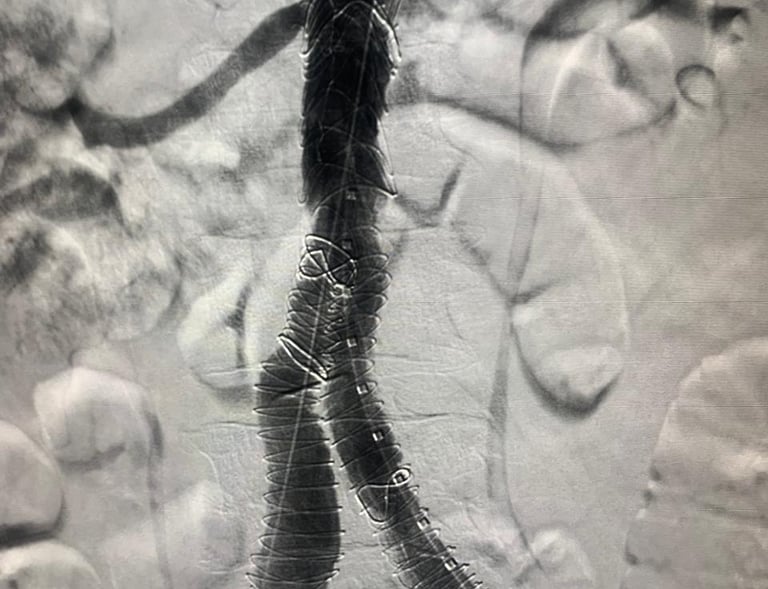

Galería

Imágenes de nuestros tratamientos en angiología y cirugía vascular.